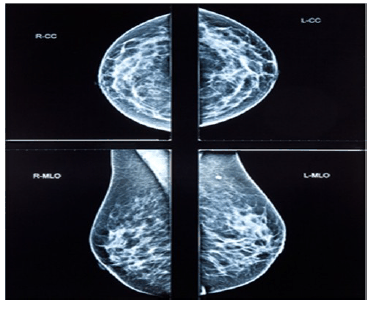

Uma paciente de 32 anos de idade, preocupada pelo fato de sua tia materna ter falecido por um câncer de mama aos 58 anos de idade compareceu à consulta e o médico solicitou uma mamografia digital. A imagem do exame realizado é apresentada a seguir.

O laudo do exame revela mamas densas com ausência de nódulos, apresentando linfonodos no respectivo prolongamento axilar, com pequenos cistos distribuídos em ambas as mamas com até 3 mm de diâmetro em sua dimensão máxima. O radiologista atribuiu a classificação BIRADS escore 2 para ambas as mamas.

Considerando esse caso clínico e os conhecimentos relativos ao rastreamento do câncer de mama, julgue os itens a seguir.